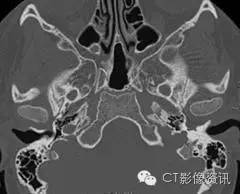

病史 10岁男孩,左侧耳聋(传导性耳聋为主)。无疼痛或者耳鸣症状。耳镜可见该患者后鼓室内有一紫色肿块并伴随鼓膜活动性下降。患者否认其它病史及肿瘤、耳聋家族史。

1.左侧卵圆孔异常?(单选)

2.上图所见提示左侧脑膜中动脉缺如?(单选)

3.左侧颈内动脉所见说明什么?(单选) 异常走行起源于颈内动脉 异常走行起源于颈外动脉分支 正常血管有一个裂口 在岩段水平部会有逆流

4.还有什么其它发现?(单选) 永存三叉动脉 永存耳动脉 中耳血管瘤 永存镫骨动脉